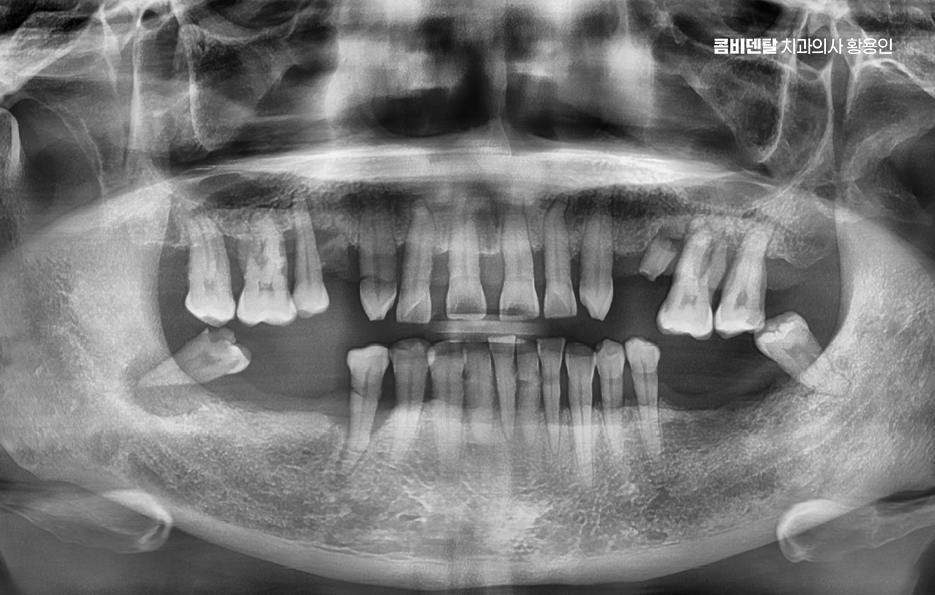

어금니 발치후 임플란트 안하면 먼저 생기는 문제는 치아 이동 현상으로 사람의 치아는 서로 의지하면서 균형을 맞추고 있는데, 어금니 하나가 빠지게 되면 그 자리를 메꾸기 위해 옆 치아들이 점점 쓰러지듯이 기울어지며 또 위아래 맞물리던 치아는 상대 치아가 사라지면 아래로 내려오거나 위로 솟구치면서 위치가 틀어질 수 있어요

결국 전체 치열이 뒤틀리고 교합이 망가지게 되는 것인데 이건 단순한 배열 문제가 아니라, 턱관절까지 영향을 줄 수 있는 변화로 이어지는 거예요.

그리고 사실 골 흡수의 문제가 무척이나 큰데 즉 잇몸뼈가 점점 사라지는 현상으로 치아가 뿌리로 잇몸뼈에 자극을 주고 있어야 뼈가 유지되는데, 치아가 빠진 상태로 계속 방치되면 그 부위 뼈는 서서히 꺼지듯이 흡수되기 시작하는 거예요.

이게 심해지면 나중에 임플란트를 하고 싶어도 뼈가 부족해서 뼈이식까지 같이 해야 하고, 수술 범위도 커지는 것이며 임플란트를 하지 않고 방치한 시간이 길수록 치료가 까다로워지고, 비용도 더 많이 들어가는 문제가 발생될 수 있었어요

나에게 맞는 치료를 하기 위해서는 정확한 진단과 설계가 중요하며 CT 촬영 등을 통해 신경 위치, 뼈의 양, 두께 등을 정밀하게 진단한 다음, 교합과 치열 구조에 맞는 위치에 임플란트를 심는 게 중요한데 잘못된 위치에 심어지면 오래 쓰기 어렵고, 나중에 통증이나 염증이 생길 수 있었어요.